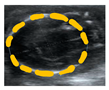

3.2. Placental Biometry

Placental thickness, placental length, and transversal area of the placenta were visualized from G25 until term. These parameters were found to increase with gestational age and fitted to a quadratic function (Figure 2A–C). The perimeter and area of discoid placental view were also fitted to a quadratic line with a low determination coefficient. Placental discoid area was difficult to quantify in ultrasound assessments performed after G50, as the placental diameter was larger than the maximum dimension of the screen (Figure 2D,E). Lastly, placental volume was calculated, and the best fit was obtained when placental weight was fitted to a straight line (Figure 2F).

Figure 2.

Placental biometry across pregnancy. Guinea pig placental (A) thickness, (B) length, (C) transversal area axis, (D) discoid perimeter, (E) discoid area, and (F) estimated placental volume, and their best fit from gestational day 25 to the end of pregnancy. Each dot represents an individual measurement (n = 47 from 19 litters). Black line = data best fit. Magenta dashed lines = 95% CI.